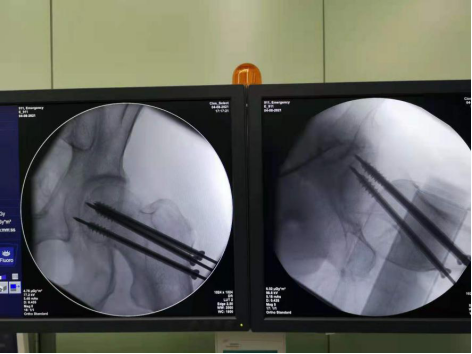

手术中精准置钉

真正的微创——均一次置钉,与术前规划完全精准匹配